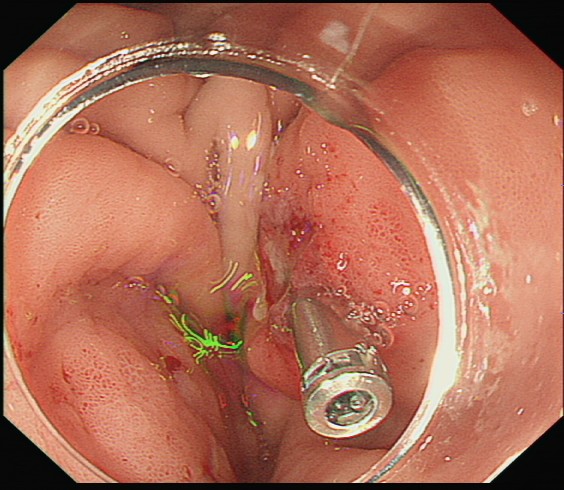

面对危急情况,高新生主任团队凭借丰富的临床经验和成熟的内镜技术,借助透明帽辅助清晰暴露视野,再用异物网篮精准抓取枣核,成功避开其锋利边缘,将这枚 “致命异物” 完整取出。随后,医生用钛夹如同 “内部缝合针”,牢牢封闭了溃疡创面。经过 5 天的住院观察,赵大娘腹痛症状明显缓解,复查结果正常后顺利出院。